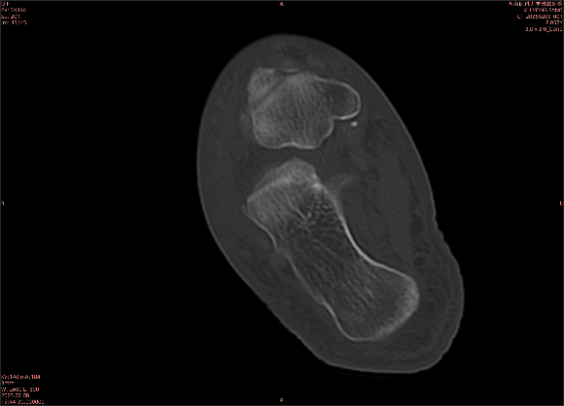

舉例圖像

圖2

專業(yè)解釋看不懂沒關(guān)系,大家看圖1和圖2就可以了,這是同一個(gè)患者跟骨的磁共振和CT圖像,圖1的紅色箭頭指示的黑線就是磁共振圖像顯示的骨折線,一目了然。而對比圖2的CT圖像上并未顯示異常。

這下大家明白了吧,如果懷疑隱匿性骨折優(yōu)先選擇磁共振檢查